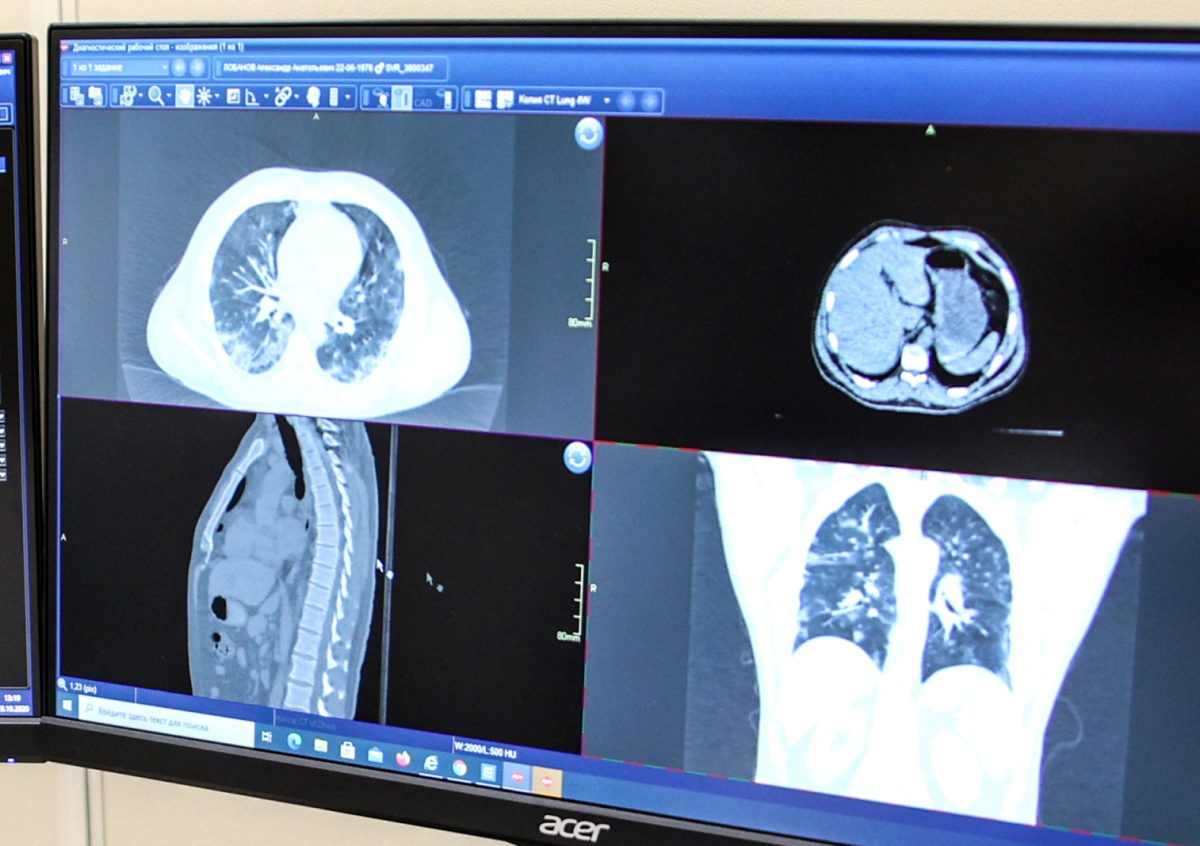

Telegram-канала Baza сообщил, что врачи зафиксировали ухудшение состояния актера Павла Баршака, госпитализированного после драки со знакомым его подруги на юго-западе Москвы. По данным канала, медики выявили отрицательную динамику после компьютерной томографии грудной клетки.

Сейчас актер находится в торакальном отделении больницы. Врачи диагностировали у него пневмоторакс (скопление воздуха), гидроторакс (скопление избыточной жидкости в легких), а также переломы ребер. Баршак находится под постоянным наблюдением медиков.